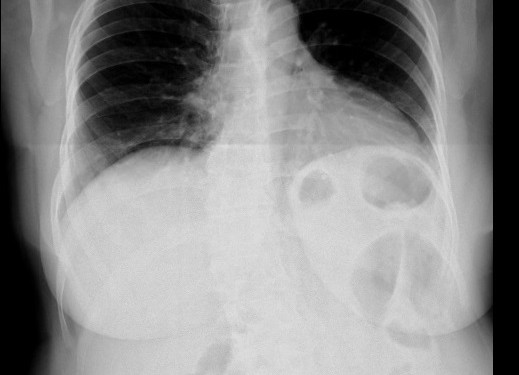

61 yaşında bayan hasta 3 gündür tekrarlayan sol üst kadran da karın ağrısı vardır. Hastanın çekilen Pa Akciğer grafisi aşağıdadır.

Tanınız nedir?   karin agrisi

hidatik kist? diafram hernisi?

Diafram hernisi doğru yanıttır.